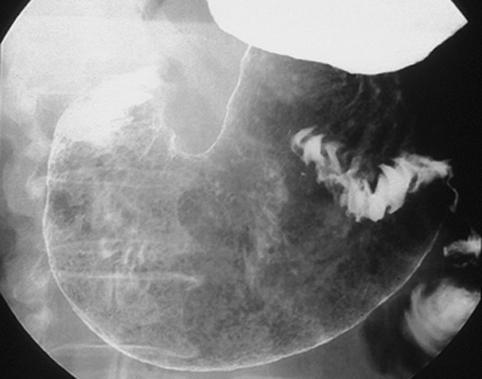

疾病(病理主体)的分类恶性上皮性肿瘤/腺癌

部位(按器官分)胃(部位)/胃角

检查方法X线

肿瘤的肉眼分类0型(表在型)/IIa型(IIa+IIc)

肿瘤最大直径30~34

肿瘤的深度m